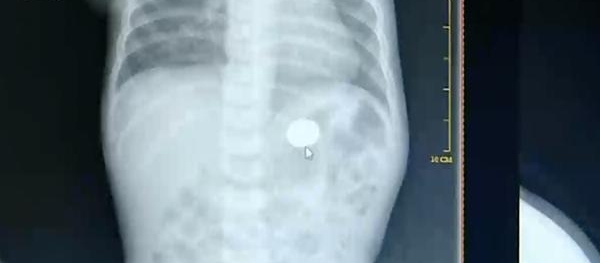

日前,宝安区一名一岁多的男婴在家中摔伤,被父母送到就近的宝安区妇幼保健院接受治疗。院方例行对小孩周身检查,发现小孩的胃部,有一块硬币大小的阴影。

宝安区妇幼保健院小儿外科医师赵冠聪:“小孩的家长跟我们讲,小孩确实是有玩硬币的习,就是在家里经常会拿着硬币在手里面玩,所以我们确认这是个硬币。”

经过两个小时的时间,儿科医生为患儿取出了藏在胃底的那枚一角钱硬币。目前,患儿已经痊愈出院。医生也提醒,近些年儿科接诊的患儿中,出现意外伤害,吞咽异物等突发情况有增多趋势,家长应加强照料,提高安全意识。